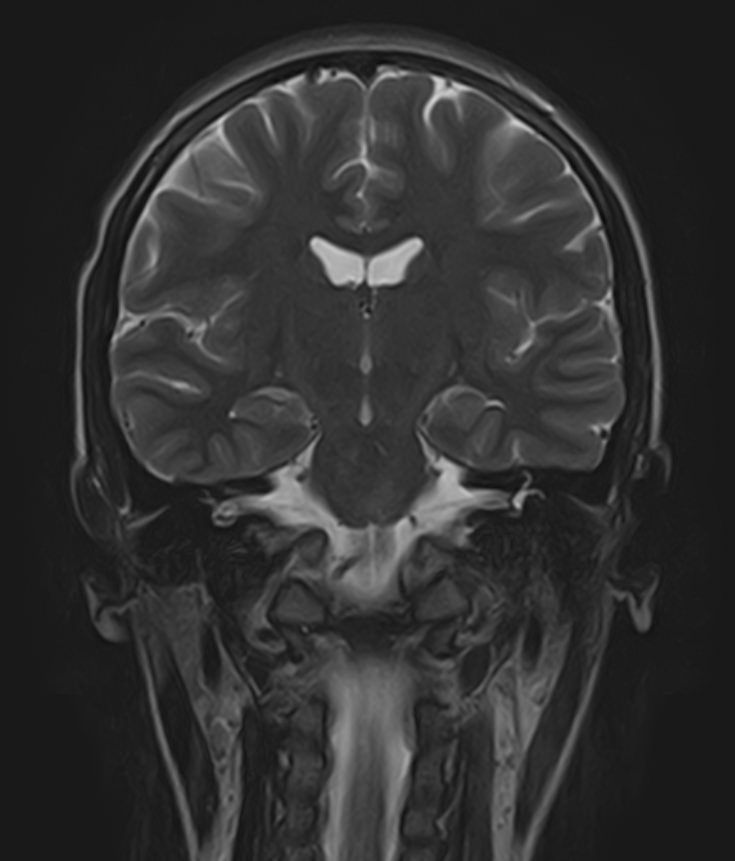

МРТ головного мозга является наиболее информативным, безопасным и доступным методом исследования, который позволяет оценить состояние всех структур и сосудистой системы головного мозга, выявить возможные патологические процессы.

Что показывает МРТ головного мозга

С помощью  магнитно-резонансной томографии можно диагностировать следующие патологии: